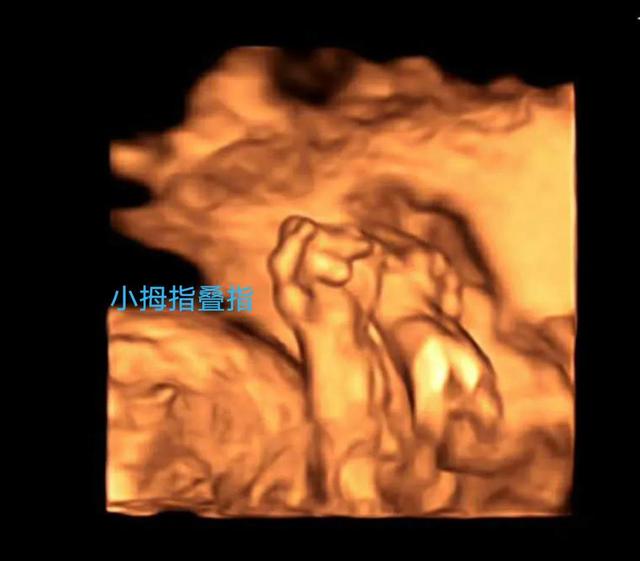

案例3

病例2、3、4清晰的三维成像让临床医生的指导更加精准,马宝和家人对诊断更加信服,也能及时做出下一步选择,将危害降到最低!